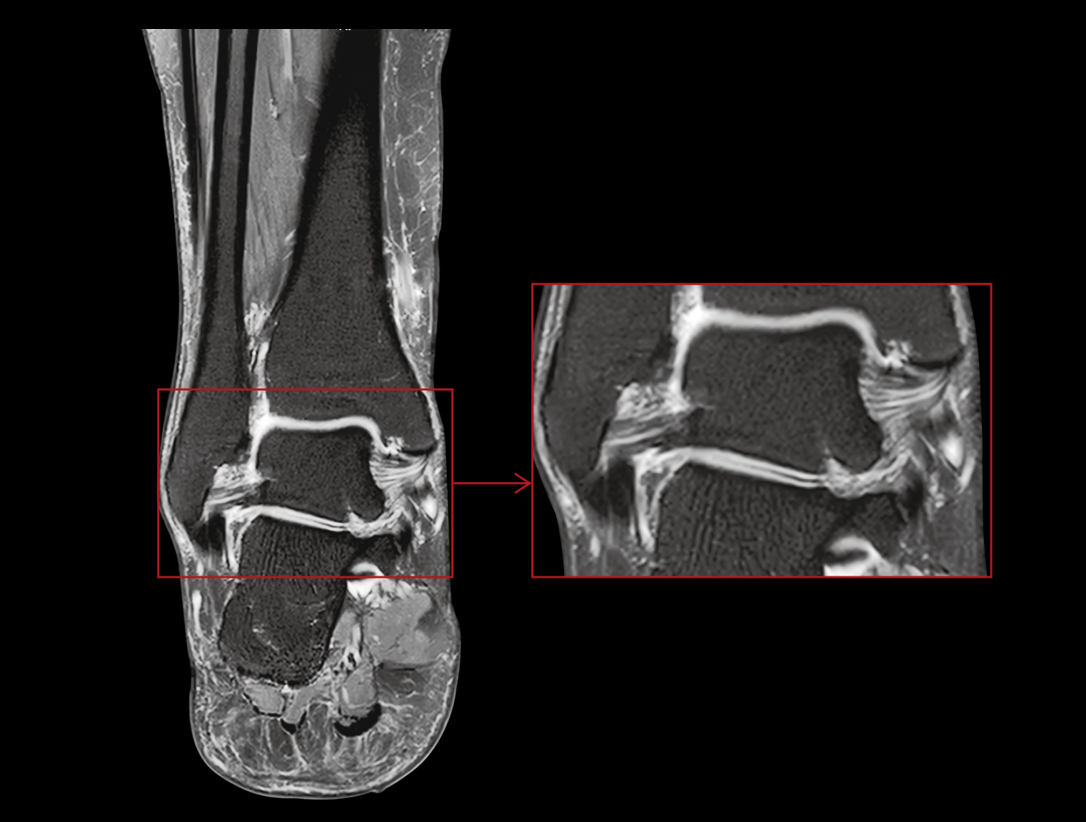

以开创性的光梭®2.0成像平台,超越用户对压缩感知的原有期待,实现2D/3D/4D全身全序列覆盖、「零」延时实时重建、动态增强亚秒级0.5s/期时间分辨率,让效率与精准兼备,开启光梭®成像新时代。